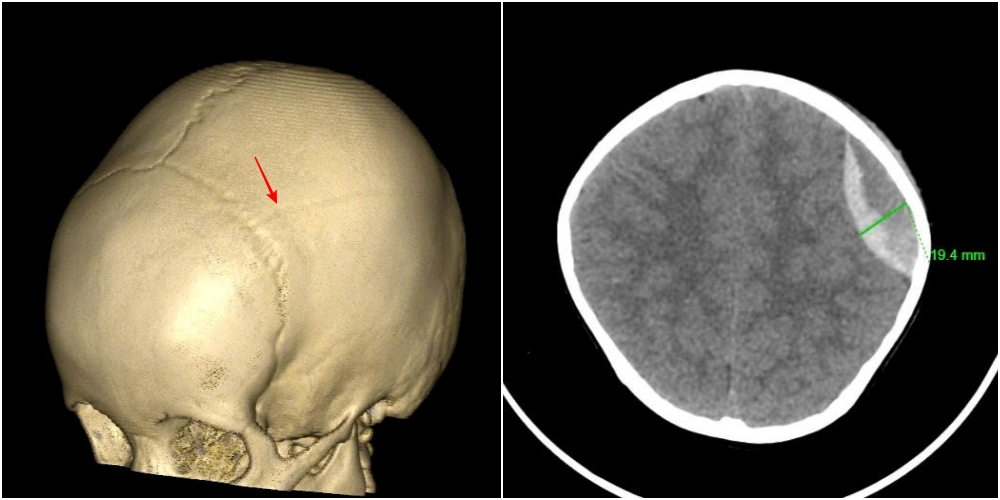

Hình ảnh vỡ xương sọ, tụ máu ngoài màng cứng đỉnh trái của bệnh nhi 3 tuổi.

Kết quả chụp cắt lớp vi tính cho thấy, hình ảnh vỡ xương sọ, chảy máu ngoài màng cứng đỉnh trái. Các bác sĩ chẩn đoán bệnh nhi bị chấn thương sọ não do ngã, vỡ xương, tụ máu ngoài màng cứng đỉnh trái.